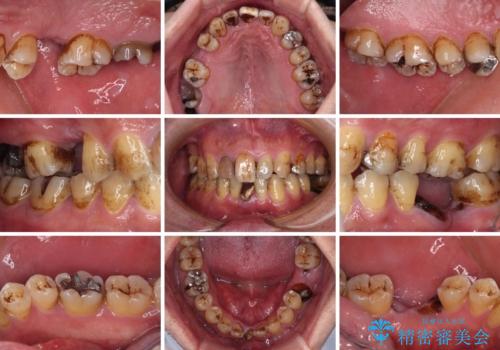

- むし歯治療途中で放置された歯が多く、スペースができたり歯が寄って来たりしているのを気にして来院された患者様です。

矯正治療を行いながら、欠損部はインプラントによる補綴治療を希望されたため、補助装置を用いたワイヤー矯正によりスペースを確保しながら歯列を整え、適宜インプラントを埋入していくこととしました。

上顎前歯もインプラントを希望していらっしゃいましたが、両隣の歯根が近接しており、インプラントは困難と判断したためオールセラミックブリッジによる補綴治療を前提として治療を開始することとしました。